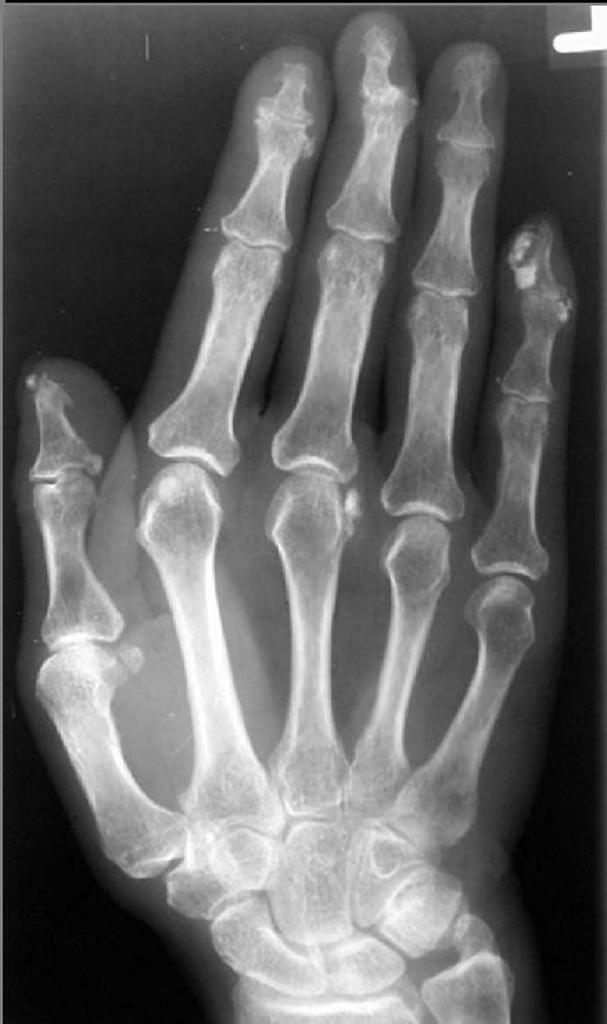

dystrophic soft tissue calcs plus acroosteolysis

scleroderma

Acroosteolysis and dystrophic soft tissue calcs

fingertips affected first with atrophy of the distal soft tissues